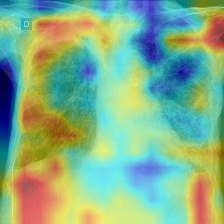

We produce localization maps by computing Ablation-CAMs for our models, applied to over 100 images from the COVIDx test split. These maps highlight image regions deemed important by the model for classifications. Figures 2(a) and 2(b) show three example COVID-positive images and localization maps computed on the Swin-B model (200-epoch). Figure 2(c) shows corresponding maps produced by the ResNet-50 baseline model on the same images.

The localization maps produced by Swin Transformers highlight the lung area, successfully focusing on the ground glass pattern, consolidation and peripheral linear opacities used by human doctors for diagnosis (Cleverley et al., 2020). In contrast, maps produced by the ResNet-50 are less successful, highlighting irrelevant areas such as shoulders and arms, sometimes missing the lungs entirely.